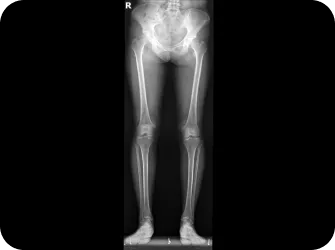

척추 엑스레이 검사

다리길이 엑스레이 검사

족저경 검사

휜다리 증상 확인